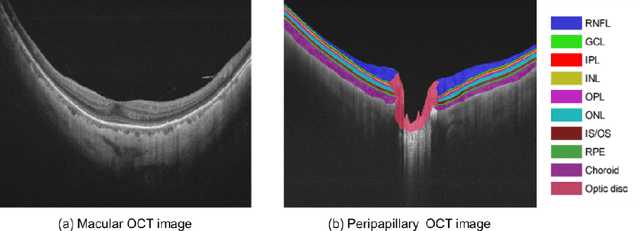

Abstract:An accurate and automated tissue segmentation algorithm for retinal optical coherence tomography (OCT) images is crucial for the diagnosis of glaucoma. However, due to the presence of the optic disc, the anatomical structure of the peripapillary region of the retina is complicated and is challenging for segmentation. To address this issue, we developed a novel graph convolutional network (GCN)-assisted two-stage framework to simultaneously label the nine retinal layers and the optic disc. Specifically, a multi-scale global reasoning module is inserted between the encoder and decoder of a U-shape neural network to exploit anatomical prior knowledge and perform spatial reasoning. We conducted experiments on human peripapillary retinal OCT images. The Dice score of the proposed segmentation network is 0.820$\pm$0.001 and the pixel accuracy is 0.830$\pm$0.002, both of which outperform those from other state-of-the-art techniques.